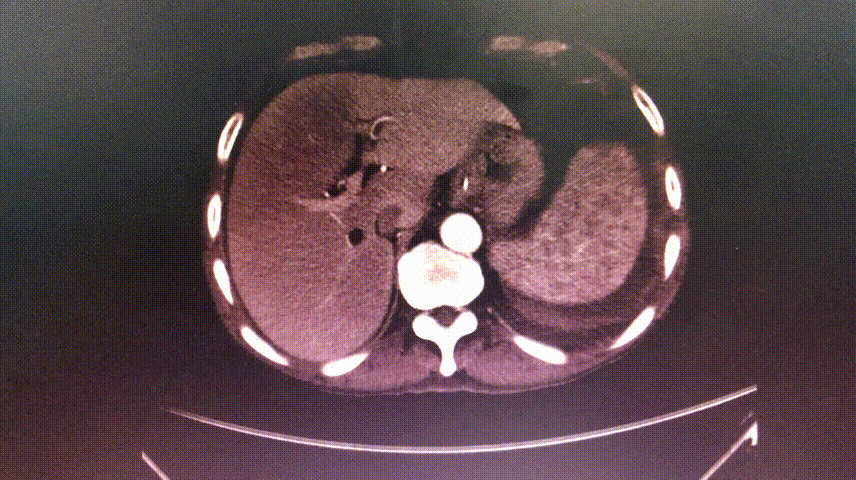

根部解剖:

术后行急诊CT检查